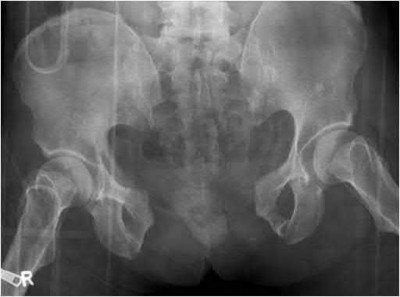

Question 11

A poly-trauma patient presents hemodynamically unstable with an anteroposterior compression (APC-III) pelvic ring injury. A circumferential pelvic binder is requested to reduce pelvic volume and control hemorrhage. To be anatomically effective, the binder must be centered precisely over which of the following landmarks?

Explanation

For optimal mechanical advantage and effective reduction of an 'open book' pelvic fracture (APC type), a pelvic binder must be applied directly over the greater trochanters of the femurs. Applying it higher, such as over the iliac crests, is a common error that fails to adequately close the pelvic ring and can paradoxically open the true pelvis.